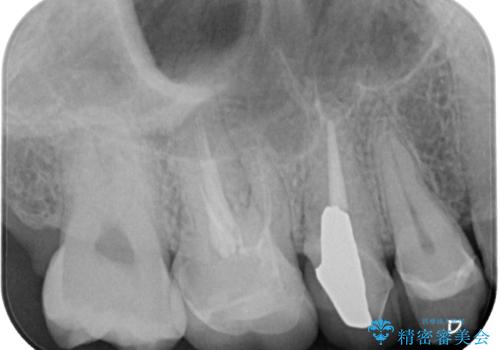

- セラミックが欠けたとのことで来院された患者様です。新しくセラミックを作り直していく治療計画としました。

拡大鏡視野下で、セラミックの被せもの、虫歯の除去を行い、オールセラミッククラウンに適した形に整えました。

咬み合わせが強く以前のセラミックを割ってしまっているので就寝時にはナイトガードを使ってもらう予定です。